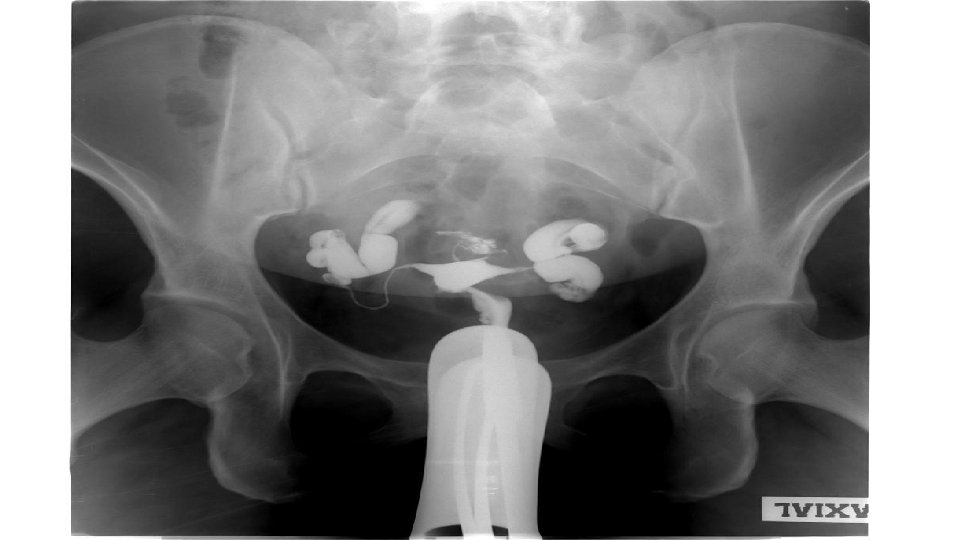

Chronic PID Investigations: . Pelvic ultrasound fixed RVF uterus, cystic pelvic mass . HSG tubal obstruction, hydrosalpinx . D laparoscopy pelvic adhesions (frozen pelvis) pelvic mass

Chronic PID • Treatment * infertility problem - ART ( ICSI ) - Tubal ligation before ICSI (hydro or pyosalpinx ) - Laparoscopic adhesiolysis